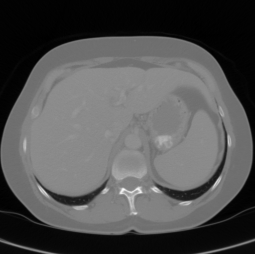

In clinical routine, manual or semi-manual segmentation techniques are applied to interprete CT and MRI images that have been acquired in the diagnosis of the liver. These techniques, however, are subjective, operator-dependent and very time-consuming. In order to improve the productivity of radiologists, computer-aided methods have been developed in the past. However, an automated robust segmentation of combined liver and lesion remains still an open problem because of challenges as a low-contrast between liver and lesion, different types of contrast levels (hyper-/hypo-intense tumors), abnormalities in tissues (such as after surgical resection of metastasis), size and varying number of lesions. As shown in figure 1 the heterogeneity in liver and lesion contrast is very large among subjects. Different acquisition protocols, differing contrast-agents, varying levels of contrast enhancements and dissimilar scanner resolutions lead to unpredictable intensity differences between liver and lesion tissue. This complexity of contrast differences make it difficult for intensity-based methods to generalize to unseen test cases from different clinical sites. In addition, the varying shape of lesions due to irregular tumor growth and response to treatment (i.e surgical resection) reduce efficiency of computational methods that make use of prior knowledge on lesion shape.

Refer to caption

Figure 1: Liver and liver lesions slices in CT and diffusion weighted DW-MRI as well as the corresponding histogram for liver and lesions pixels in the respective modality. The shape, size and level of contrast vary for different lesions. As the histograms indicate, there is a significant overlap between liver and lesion intensities, leading to a low overall contrast.